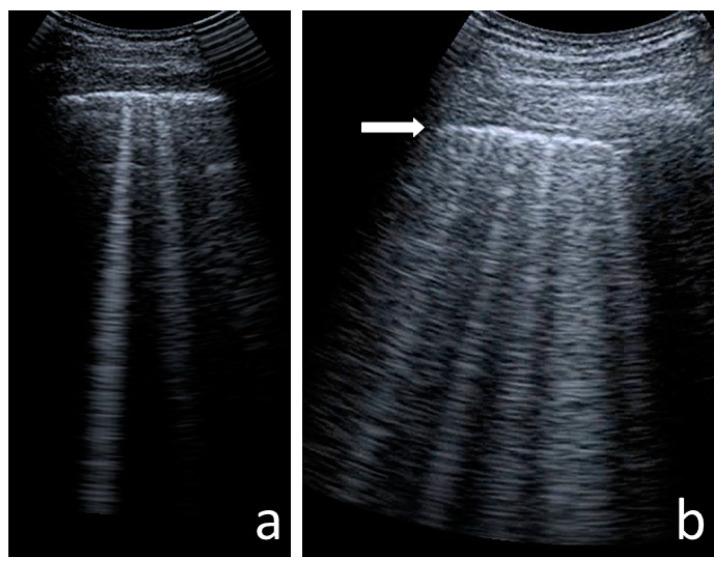

With the increasing longevity of cystic fibrosis (CF), there is a growing need to minimise exposure to ionising radiation in patients who undergo regular imaging tests while monitoring the course of the lung disease. This study aimed to define the role of lung ultrasounds (LUS) in the evaluation of lung disease severity in children with clinically stable CF. LUS was performed on 131 patients aged 5 weeks to 18 years (study group) and in 32 healthy children of an equivalent age range (control group). Additionally, an interobserver study was performed on 38 patients from the study group. In CF patients, the following ultrasound signs were identified: I-lines; Z-lines; single, numerous and confluent B-lines; Am-lines; small and major consolidations; pleural line abnormalities and small amounts of pleural fluid. The obtained results were evaluated against an original ultrasound score. LUS results were correlated with the results of chest X-ray (CXR) [very high], pulmonary function tests (PFTs) [high] and microbiological status [significant]. The interobserver study showed very good agreement between investigators. We conclude that LUS is a useful test in the evaluation of CF lung disease severity compared to routinely used methods. With appropriate standardisation, LUS is highly reproducible.

随着囊性纤维化(CF)患者寿命的延长,在对肺部疾病病程进行监测的同时,尽量减少接受常规影像学检查的患者所受电离辐射的需求日益增加。本研究旨在明确肺部超声(LUS)在评估临床病情稳定的CF患儿肺部疾病严重程度中的作用。对131例年龄在5周至18岁的患者(研究组)以及32例年龄范围相当的健康儿童(对照组)进行了LUS检查。此外,对研究组中的38例患者进行了观察者间研究。在CF患者中,识别出了以下超声征象:I线;Z线;单发、多发及融合的B线;Am线;小实变和大实变;胸膜线异常及少量胸腔积液。将获得的结果与原始超声评分进行对照评估。LUS结果与胸部X线(CXR)结果[高度相关]、肺功能测试(PFTs)结果[相关性高]以及微生物学状态[显著相关]相关。观察者间研究显示研究者之间具有很好的一致性。我们得出结论,与常规使用的方法相比,LUS在评估CF肺部疾病严重程度方面是一种有用的检查方法。通过适当的标准化,LUS具有高度可重复性。